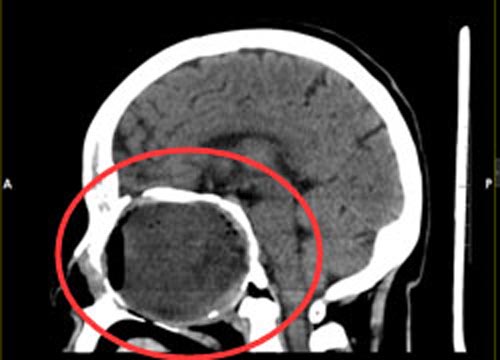

几十年间,视力由模糊不清变成了仅有光感,吕阿姨也一直没有再去医院。3年前她开始出现嗅觉丧失,近1个月来出现头痛,伴有鼻腔流液,吕阿姨和家人意识到病情严重了。当地医院头颅CT检查提示:“筛窦-蝶窦巨大囊肿”,广东三九脑科医院进一步头部MR检查显示:前颅底及筛窦-蝶窦-鼻咽部巨大占位病变,待排骨来源病变,骨化性纤维瘤可能,待排软骨来源肿瘤。

综合神经外科鲁明副院长了解病情后认为:患者前颅窝底及鼻腔巨大占位,考虑骨源性肿瘤;无手术禁忌症,家属同意行手术治疗。完善相关术前检查后,在全麻下“经右侧前颅窝额底硬膜外及鼻蝶联合入路前颅窝底及鼻腔巨大胆脂瘤切除术+颅底重建术+颅骨成形术”,手术顺利。术后,吕阿姨的双眼视力明显改善。